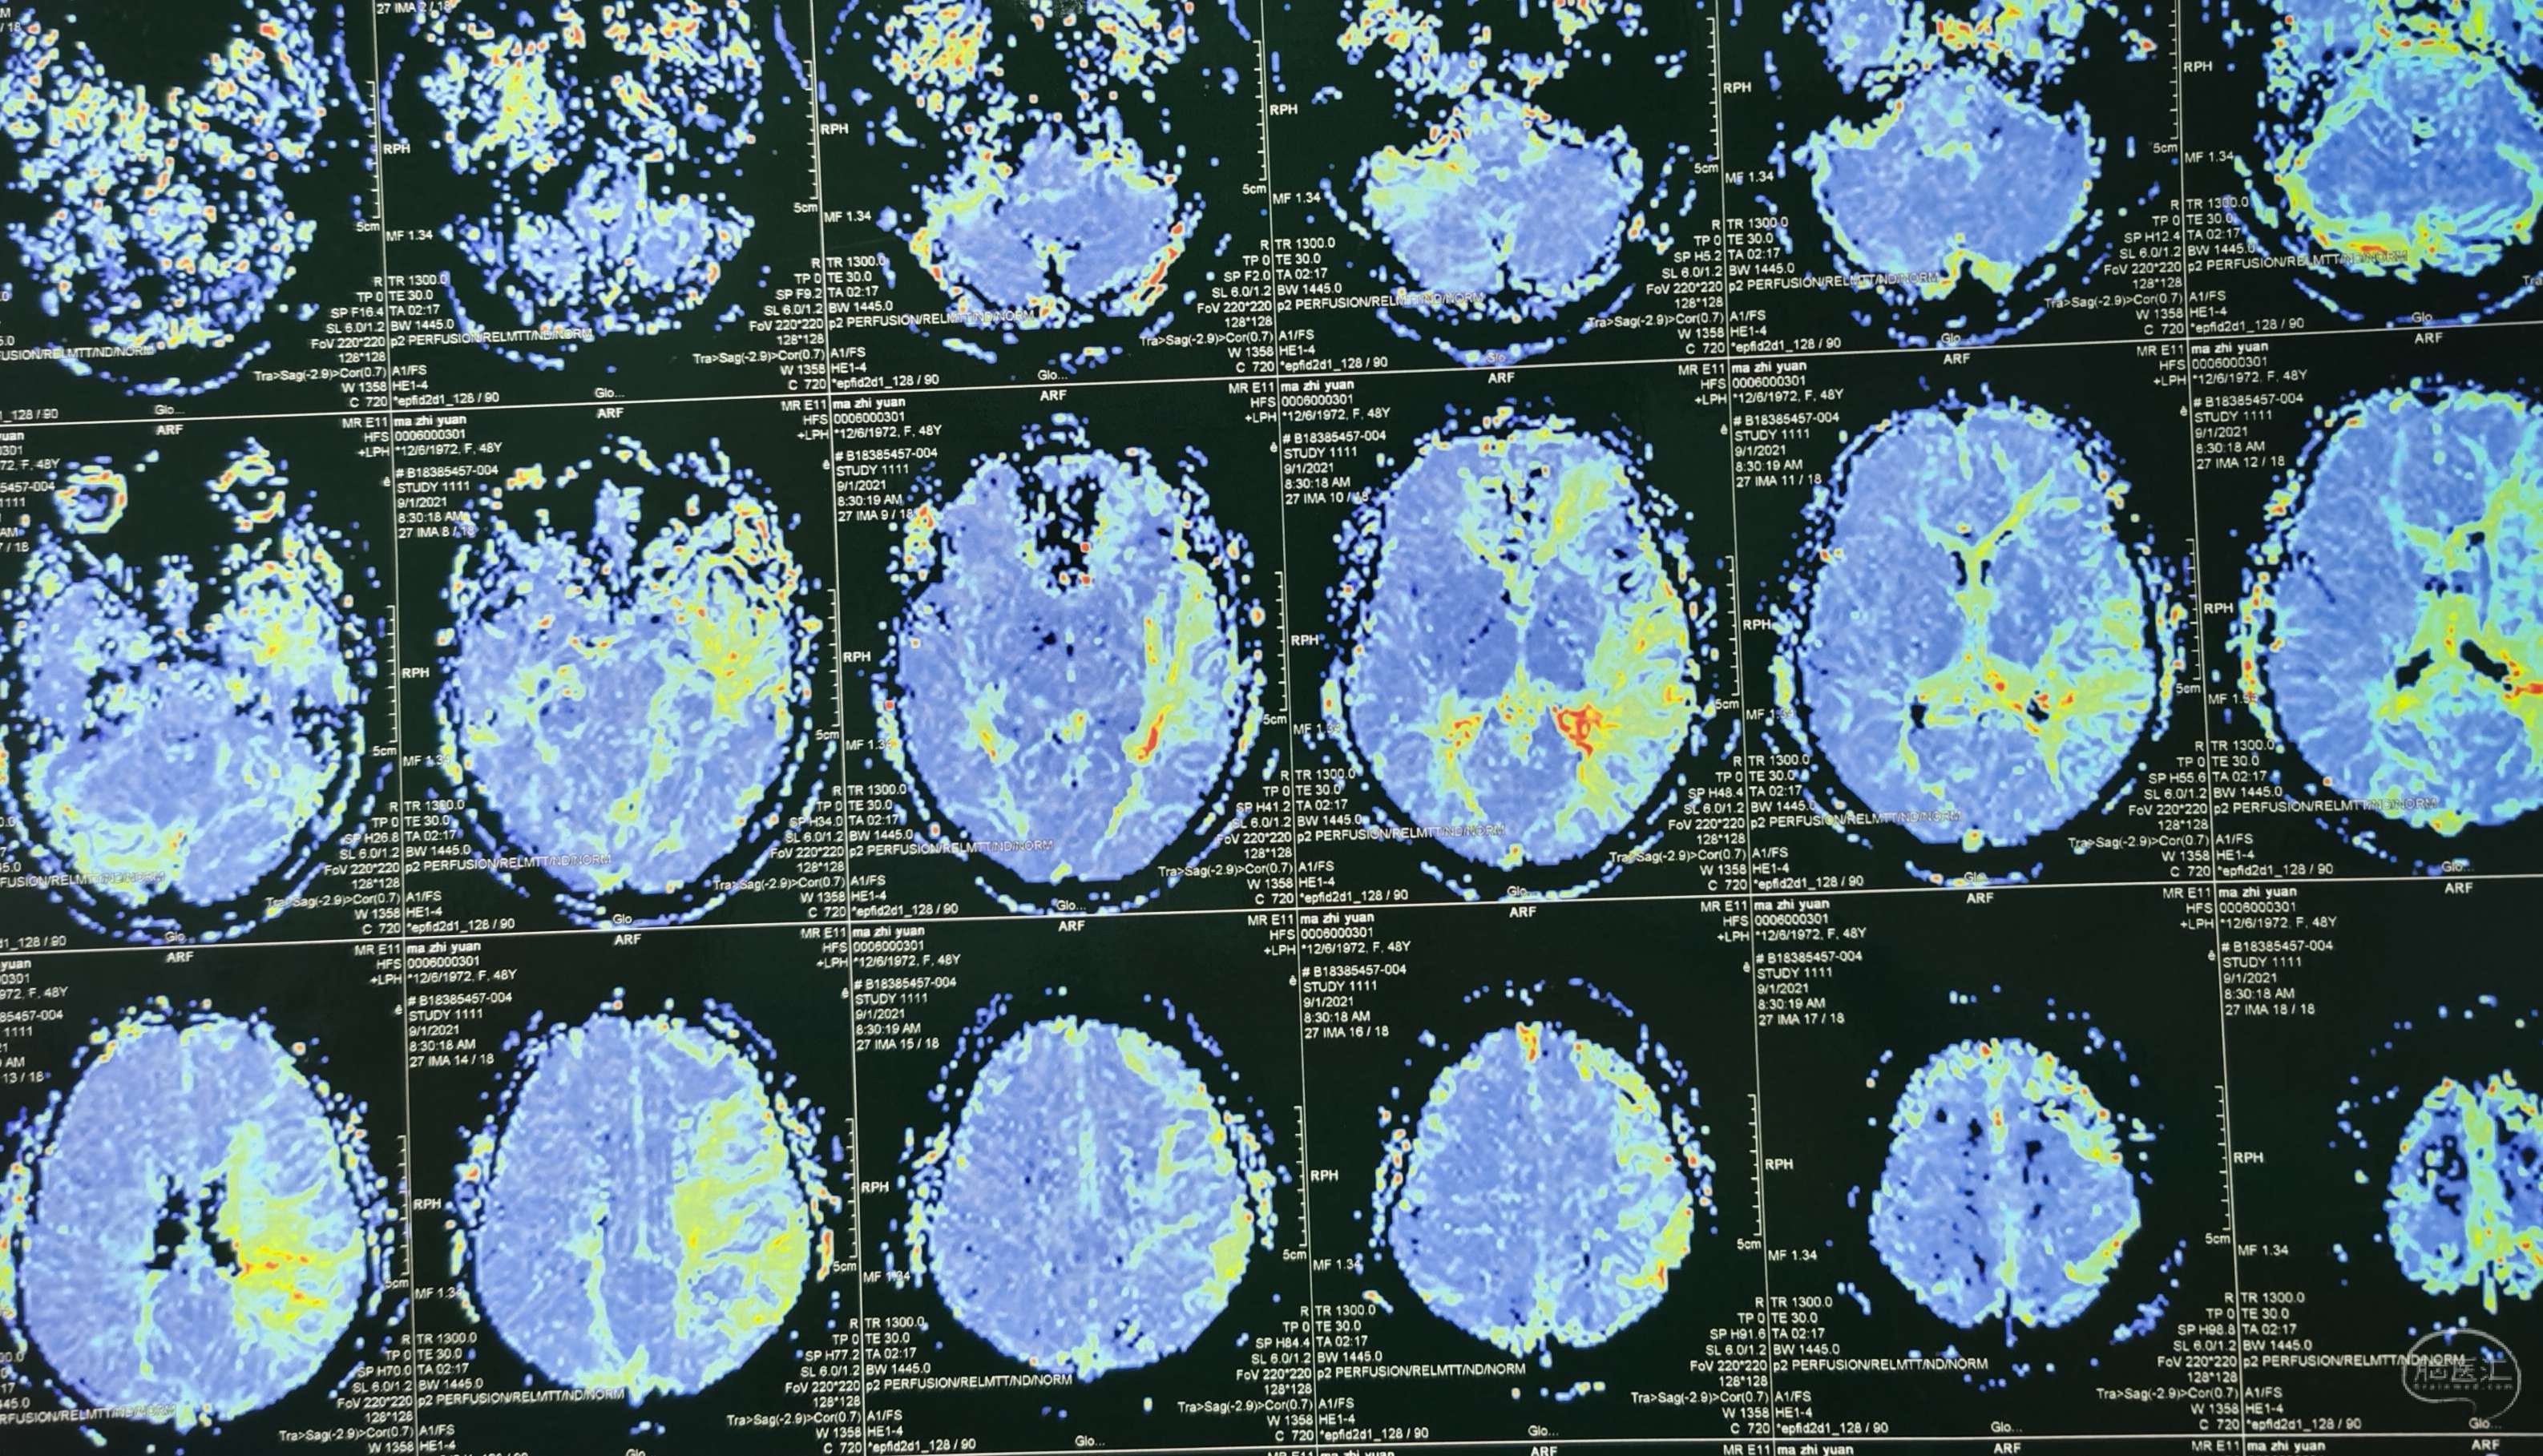

磁共振灌注提示:双侧大脑半球低灌注改变。